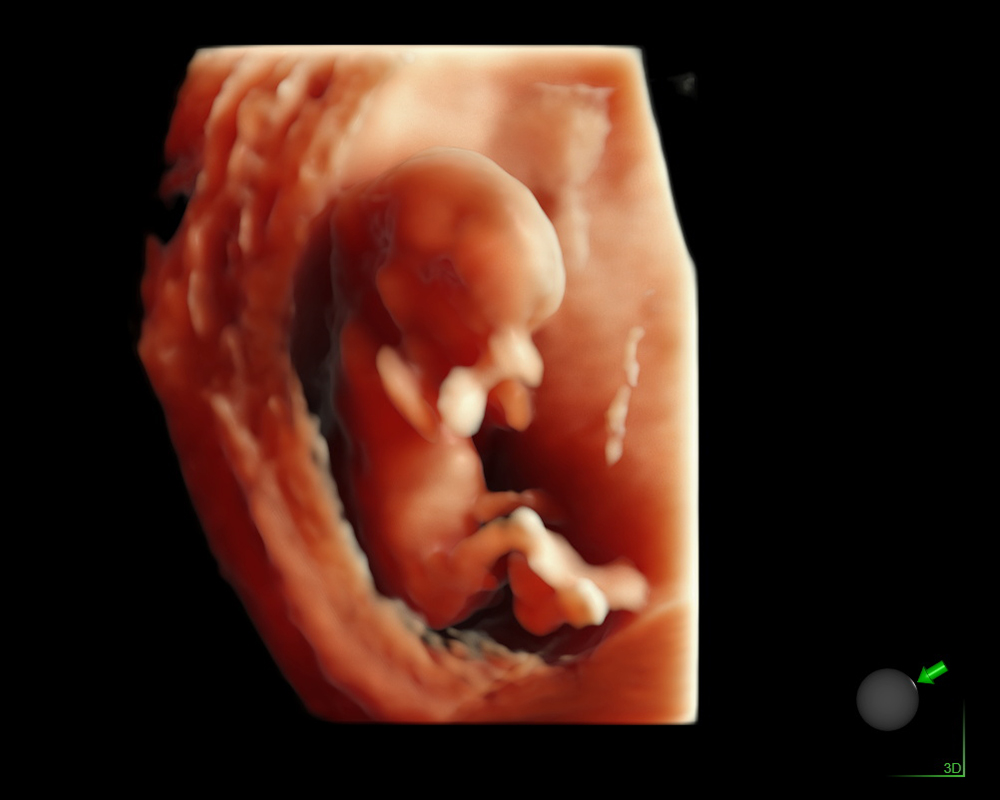

Eco Anatómico 4D

Realizado entre las semanas 20 y 30, el Eco Anatómico 4D, es un estudio que permite una valoración detallada del crecimiento, órganos y estructuras de bebé. Este eco es crucial para la detección temprana de malformaciones congénitas. Si la posición de bebé y las condiciones nos permiten, podemos llevarnos un hermoso recuerdo al tomar fotografías en 4d.